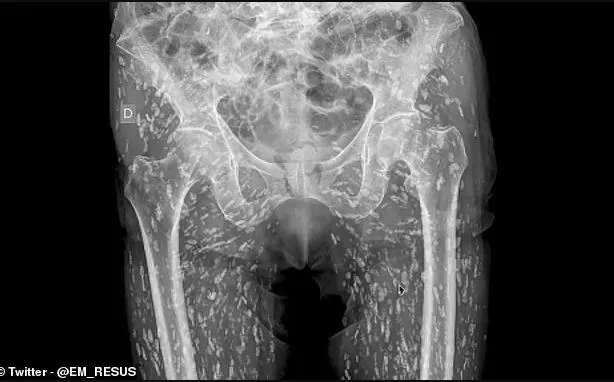

Ένας γιατρός από τη Φλόριντα, ο οποίος δουλεύει στα επείγοντα νοσοκομείου, μοιράστηκε στα μέσα κοινωνικής δικτύωσης μια από τις «πιο τρελές ακτινογραφίες» που είχε δει ποτέ.

Σύμφωνα με τον Δρ Sam Ghali, το σώμα ενός ασθενούς είχε γεμίσει με αυγά παράσιτου, μικρές κύστες στο μέγεθος ρυζιού, τα οποία «κολυμπούσαν» ελεύθερα μέσα στο σώμα του.

Ο ασθενής, που δεν κατονομάστηκε, γέμισε με το παράσιτο «ταινία» αφού έφαγε ωμό ή όχι καλά μαγειρεμένο χοιρινό, το οποίο  που περιείχε προνύμφες (σκουλήκια) ταινίας.

Οι προνύμφες  μπήκαν στους ιστούς του σώματος του και σχημάτισαν εκεί κύστες, που αν έσπαγαν, θα μπορούσαν να προκαλέσουν λοιμώξεις στον ασθενή.

Σε ένα βίντεο που έχει γίνει viral, ο σοκαρισμένος Dr Ghali λέει: «Είναι παντού (οι κύστεις) και είναι αμέτρητες, δεν μπορείς καν να αρχίσεις να τις μετράς όλες», σύμφωνα με την DailyMail

Ακόμα πιο απίστευτο είναι το γεγονός ότι ο ασθενής δεν γνώριζε ότι έπασχε από κυστικέρκωση (μόλυνση των ιστών από την προνύμφη σκώληκα ταινία των χοίρων) -  ο άνδρας είχε πάει στο νοσοκομείο για ακτινογραφία μετά από μια άσχετη πτώση.